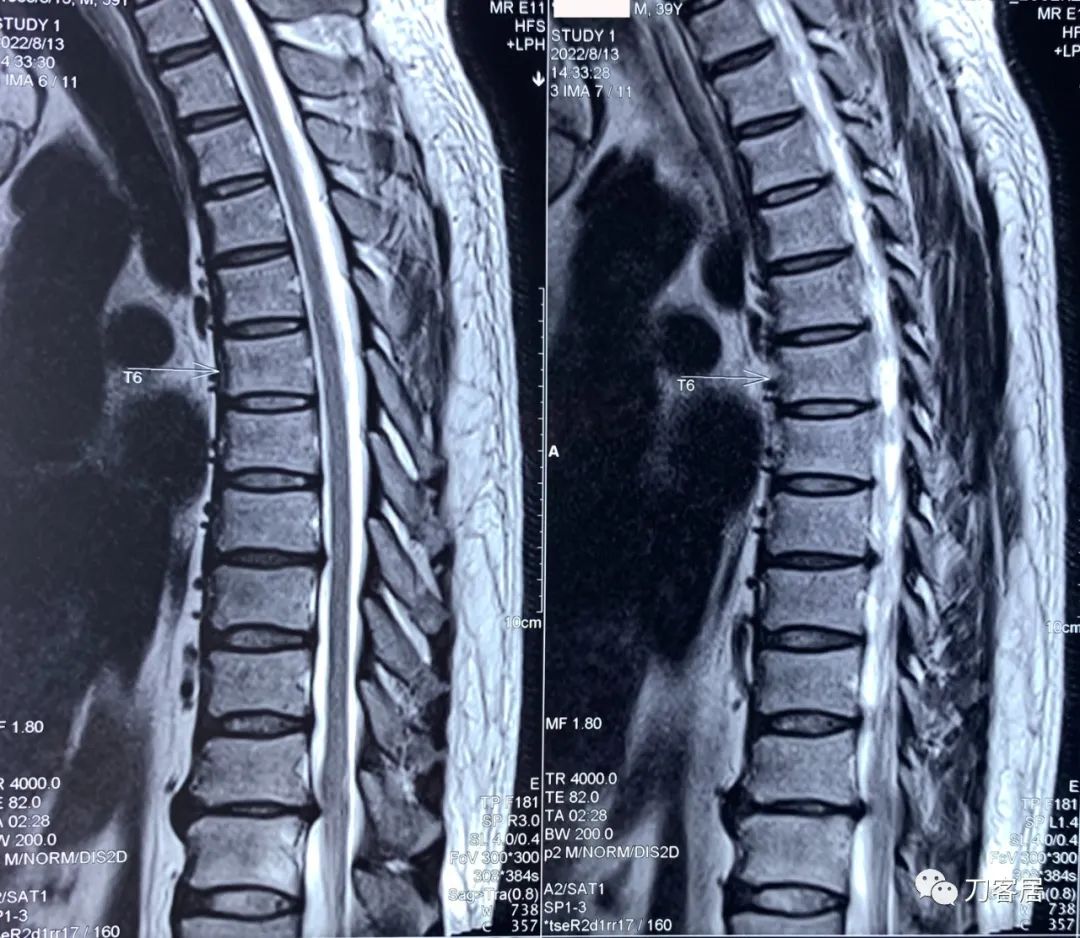

图7. 20220813西安第三方影像机构胸椎MRI01,提示胸8-9椎间盘突出,胸11-12椎间盘突出,椎管狭窄。

图8. 20220813西安第三方影像机构胸椎MRI02,提示胸8-9椎间盘突出,胸11-12椎间盘突出,椎管狭窄。

图9. 20220813西安第三方影像机构胸椎MRI03,脊髓水成像,显示胸11-12处脊髓受压。

图10. 20220813西安第三方影像机构胸椎MRI04,提示右侧隐窝狭窄,右侧黄韧带肥厚,但椎管狭窄并不那么严重。